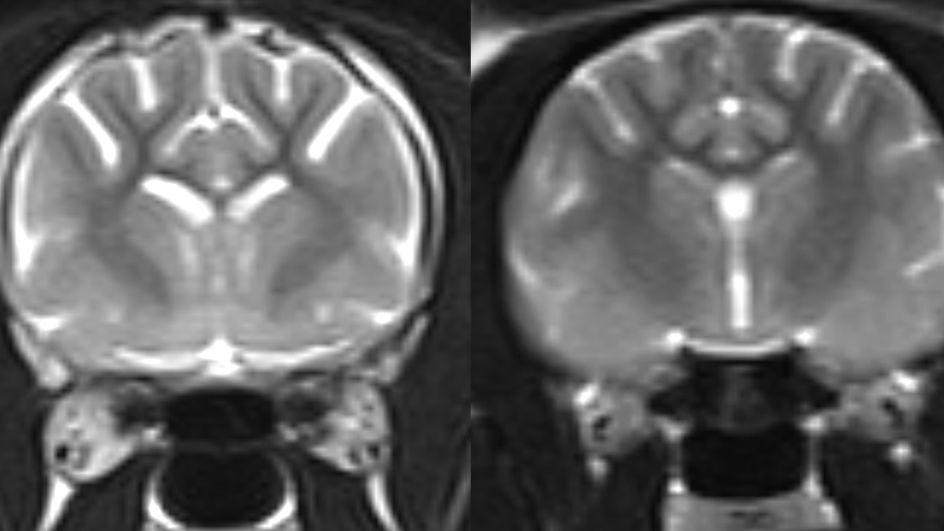

Imagens de microscopia de gatos mais velhos que anteriormente apresentaram sintomas de demência felina revelaram um acúmulo de beta-amiloide nas sinapses — as junções entre as células cerebrais.

As sinapses permitem a passagem de mensagens entre as células cerebrais, e a perda delas causa redução da memória e das habilidades de raciocínio em humanos com Alzheimer.

Os pesquisadores encontraram evidências de que células de suporte do cérebro — chamadas astrócitos e microglia — englobaram as sinapses afetadas. Esse processo, conhecido como poda sináptica, é importante durante o desenvolvimento cerebral, mas também contribui para a demência.